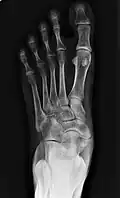

X-ray of the foot showing an accessory navicular bone

An accessory navicular bone is an accessory bone of the foot that occasionally develops abnormally in front of the ankle towards the inside of the foot. This bone may be present in approximately 2-14% of the general population and is usually asymptomatic.[1][2][3] When it is symptomatic, surgery may be necessary.

Radiological images